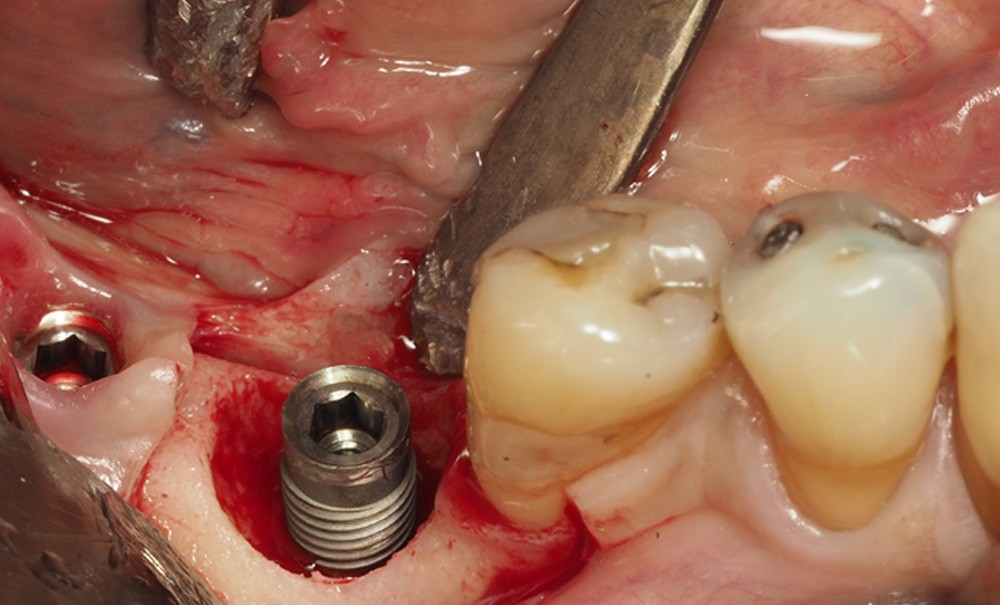

De nombreuses approches ont été décrites, mais le principal objectif de la chirurgie est de créer un accès à la surface implantaire, d’éliminer le biofilm, les dépôts calcifiés et, peut-être, les excès de ciment. La décontamination de la surface implantaire doit permettre d’arrêter la progression de la maladie et d’obtenir la cicatrisation de la lésion [8]. Des techniques régénératives ont également été décrites, celles-ci ont pour objectif de réparer le défaut intra-osseux et de permettre une ré-ostéointégration de la surface implantaire [9].

La chirurgie résectrice a pour objectif de permettre la décontamination de la surface implantaire et la modification de la morphologie des tissus péri-implantaires afin de faciliter le contrôle de plaque quotidien [8]. Cela implique l’élimination du tissu de granulation, un repositionnement apical du lambeau muco-périosté et d’éventuelles ostéoplasties et ostéotomies [10].